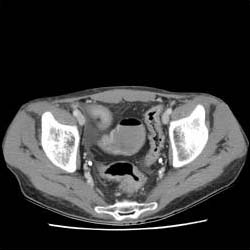

RADIOLOGY: ABDOMEN: Case# 34094: EXAM1: CROHN